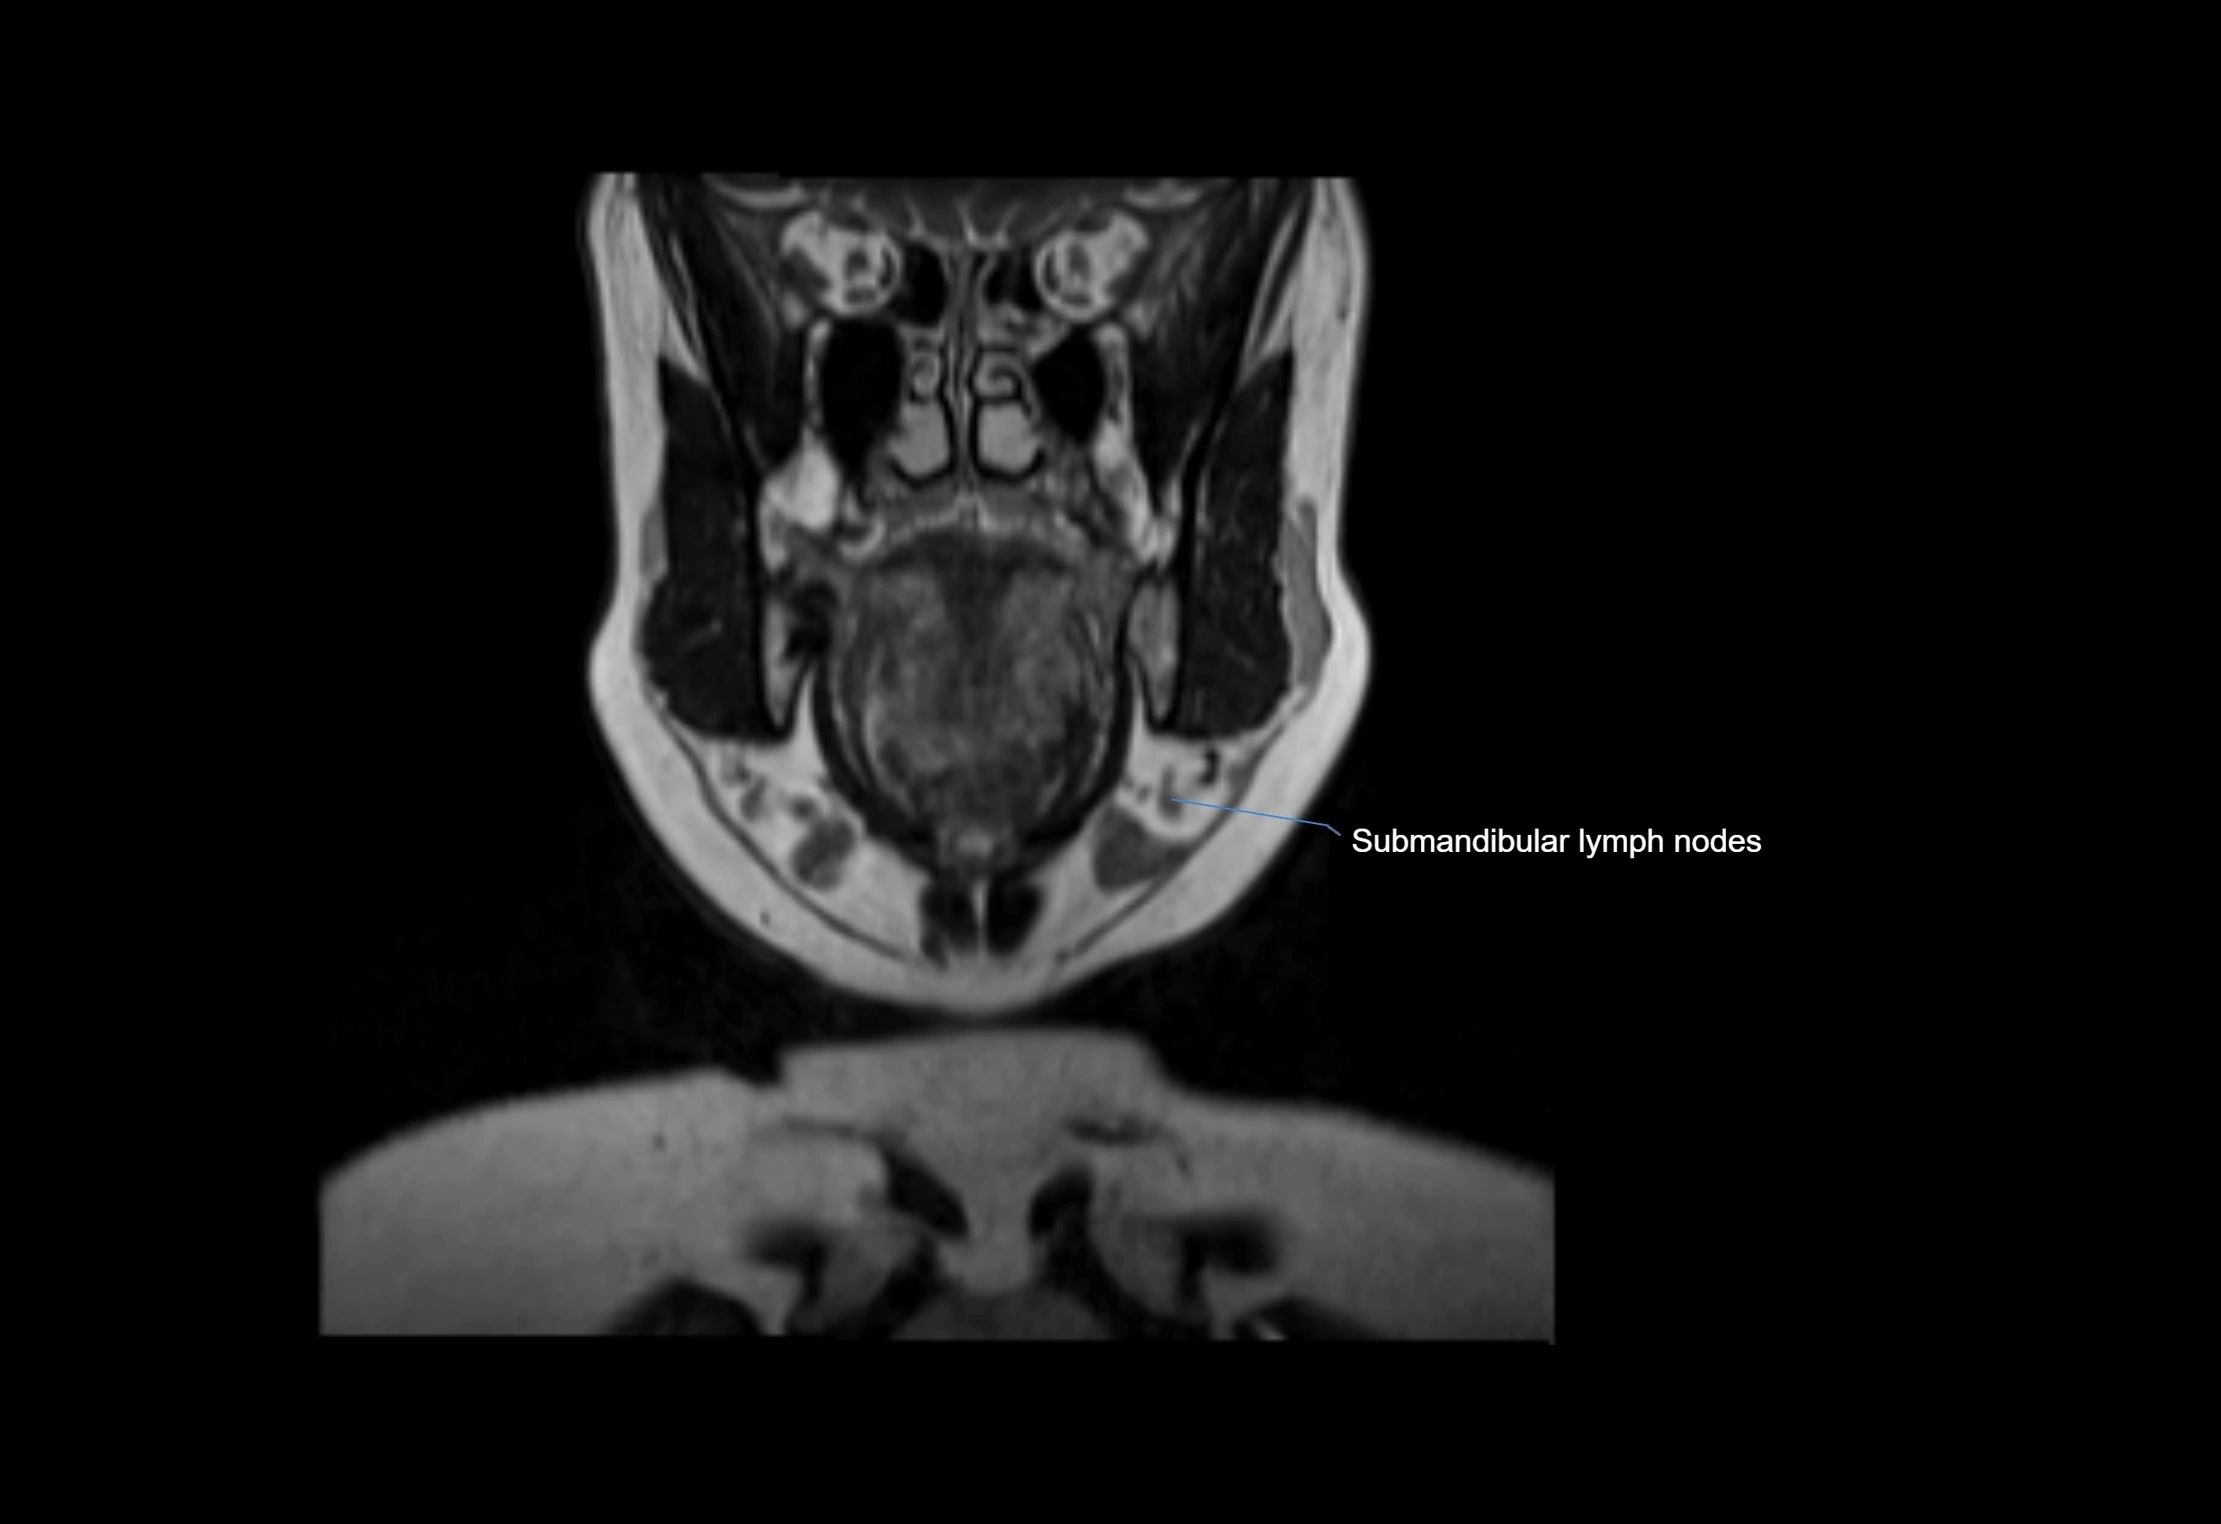

Accessory lymph nodes are small, secondary lymph nodes located along the main facial and cervical lymphatic chains, often adjacent to primary lymph nodes, such as preauricular, submandibular, or occipital nodes. They are typically less than 5 mm in diameter, embedded within subcutaneous fat or connective tissue, and may be variable in number and location. These nodes provide additional filtration and immune surveillance for lymph collected from the face, scalp, and neck regions. Accessory lymph nodes are usually non-palpable in healthy individuals but may enlarge in response to infection, inflammation, or metastasis, making them clinically significant.

Location

• Found along primary lymph node chains, including preauricular, submandibular, parotid, and occipital regions

• Embedded in subcutaneous fat or superficial fascia, often lateral or posterior to primary nodes

• Variable in number; may occur unilaterally or bilaterally, depending on individual anatomy

MRI Appearance

T2-weighted images:

• Nodes show intermediate signal, with surrounding fat bright

• Useful for detecting edema, inflammation, or infiltration

• Fatty hilum may appear slightly hyperintense relative to cortex

MRI images

image